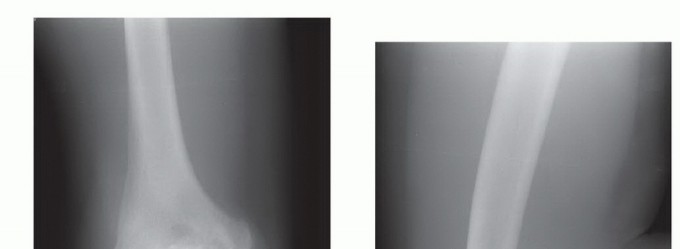

Arthroscopic Treatment of Elbow Loss of Motion DEFINITION Loss of motion is a common sequela of elbow trauma …

Arthroscopic Débridement for Elbow Degenerative Joint Disease DEFINITION Primary degenerative arthritis of th…

Arthroscopic Treatment of Chondral Injuries and Osteochondritis Dissecans DEFINITION Osteochondritis dissecan…